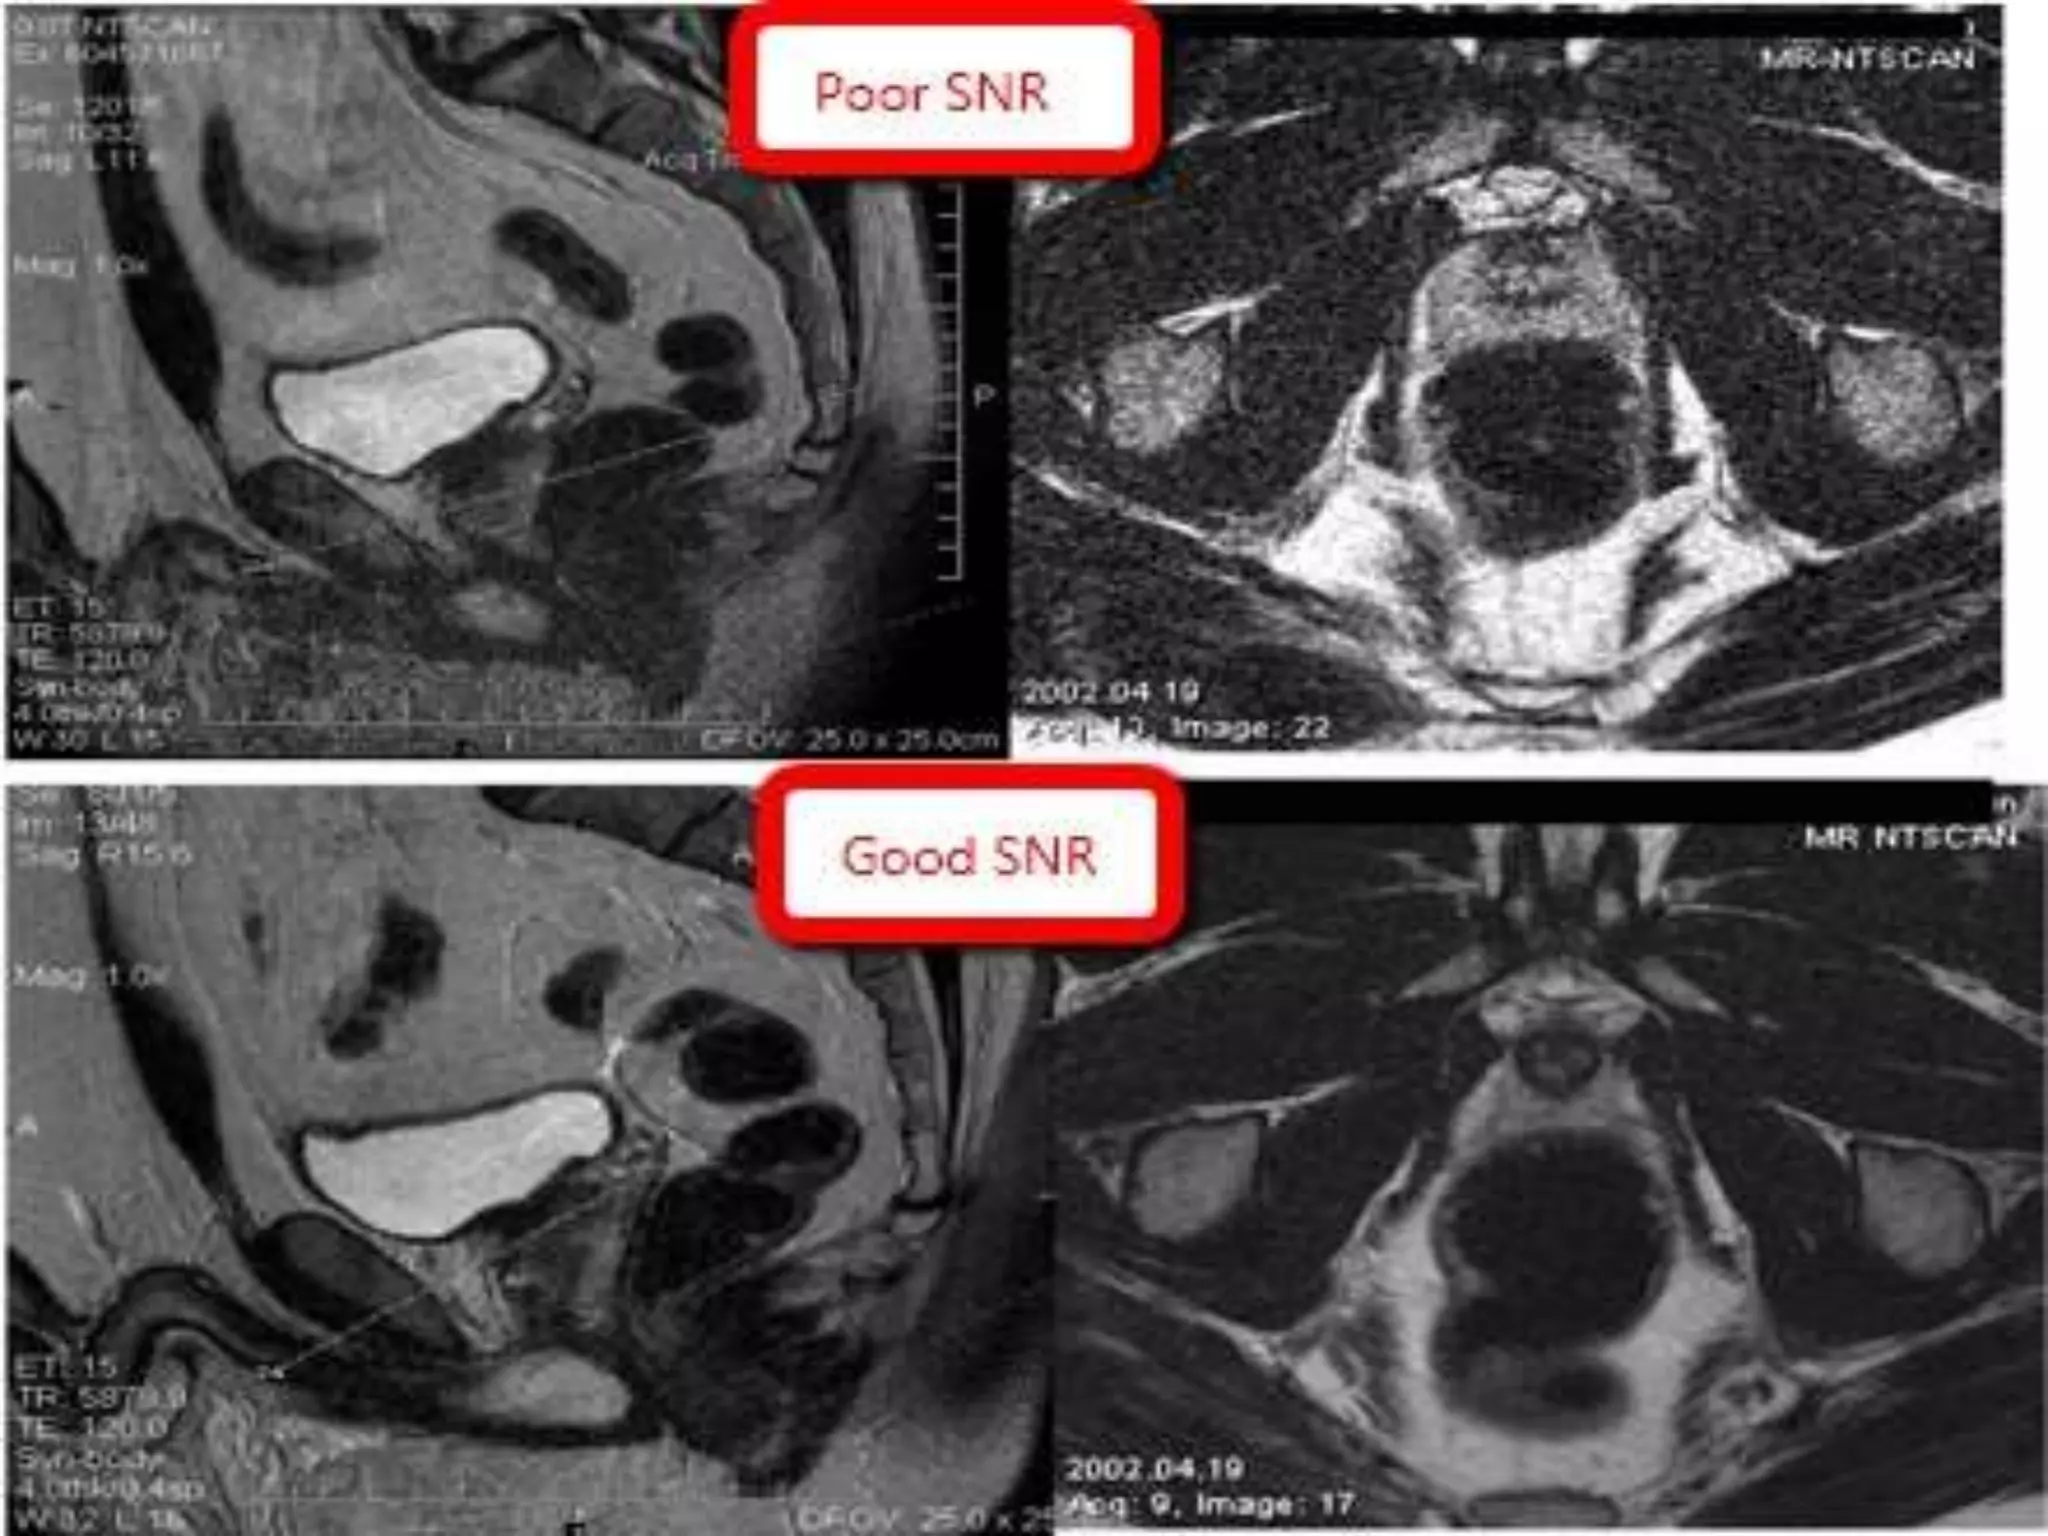

IMAGE QUALITY

• Factors that determine image quality

Signal: noise ratio ,

Contrast ,

Spatial Resolution,

Scan time.

SIGNAL : NOISE RATIO

• Noise is a random variation in the MR

signal, occurring at all frequencies and all

the time, due to -1. PATIENT(white noise)

2.ENVIRONMENT.

3. SCANNER.

• All noise reduces and obscures contrast

bbetween tissues and is worst in areas of

low PD and low signal.

IMPROVE SNR…

• INCREASING THE

SIGNAL BY

VOXEL SIZE

• DECREASING TE AND

INCREASING TR/FLIP

ANGLE.

• SE SEQUENCES > GRE

• HIGH TESLA MACHINE

• REDUCING NOISE

BY

NUMBNER OF

EXCITATIONS

• REDUCING

BANDWIDTH

• REDUCING CROSS

TALK